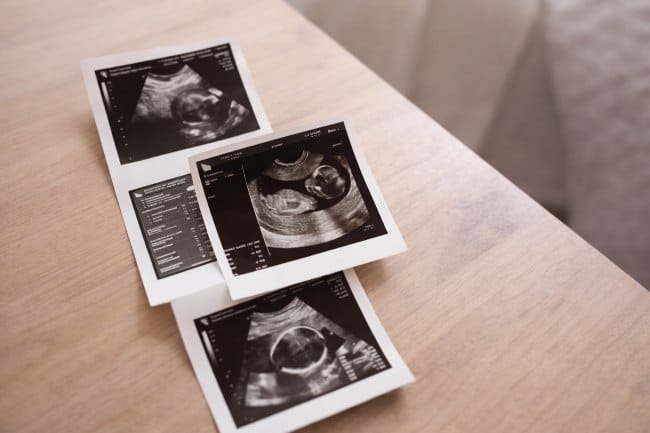

USG 2 dimensi adalah pemeriksaan ultrasonografi yang menghasilkan gambar datar hitam putih guna melihat kondisi organ tubuh atau perkembangan janin. Pemeriksaan ini umum digunakan untuk menilai struktur tubuh dan mendeteksi adanya kelainan.

USG 2 dimensi biasanya dilakukan saat pemeriksaan kehamilan. Berbeda dengan USG 3D, 4D, atau 5D yang menampilkan gambar berwarna dan lebih detail, USG 2 dimensi hanya menghasilkan gambar datar hitam-putih.

Meski sederhana, informasi yang diperoleh tetap penting untuk memastikan pertumbuhan janin normal dan mendeteksi potensi kelainan sejak dini.